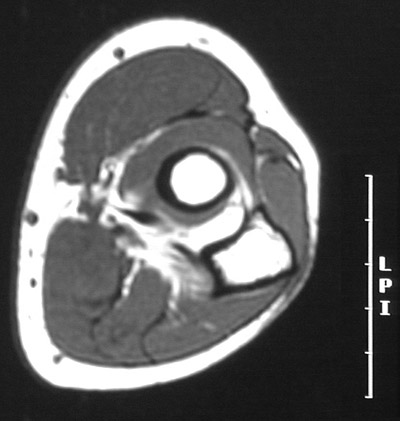

This is a normal axial T1 weighted MRI scan demonstrating the Head of radius, marrow cavity and Compact or cortical bone and Olecranon process of ulna and Biceps brachii tendon and Annular ligament and Anconeus and Extensor digitorum communis and Extensor carpi radialis brevis and Extensor carpi radialis longus and Supinator and Brachioradialis and Pronator teres and Flexor carpi radialis and Flexor digitorum superficialis and Palmaris longus and Flexor carpi ulnaris and Trunk of radial artery and Trunk of ulnar artery and Tendon of brachialis.